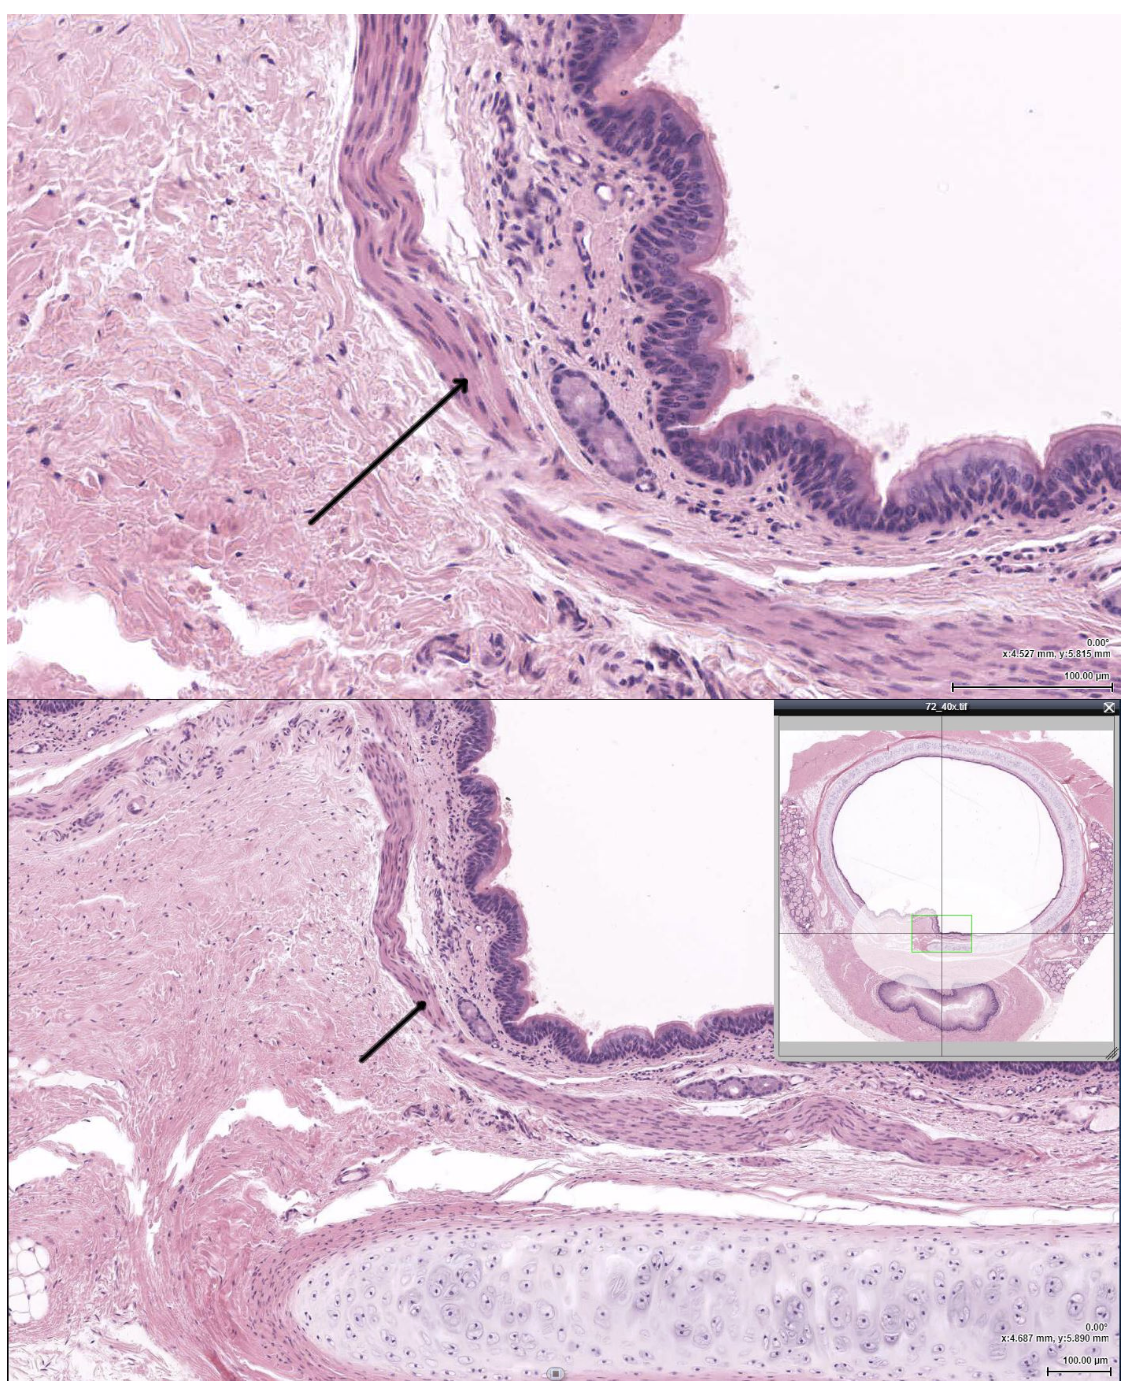

In the attached EM, the cell indicated by the arrow is most likely which of the following?

Basal cell

The structure indicated by the arrow is most likely which of the following?

Trachealis muscle

The tissue indicated by the arrow would most likely be found in which other location?

Trachea

The layer indicated by the arrow is primarily composed of which of the following?

Fibroelastic CT

Seromucous gland in submucosa

The layer indicated by the arrow is most likely which of the following?

Lamina propria of terminal bronchiole